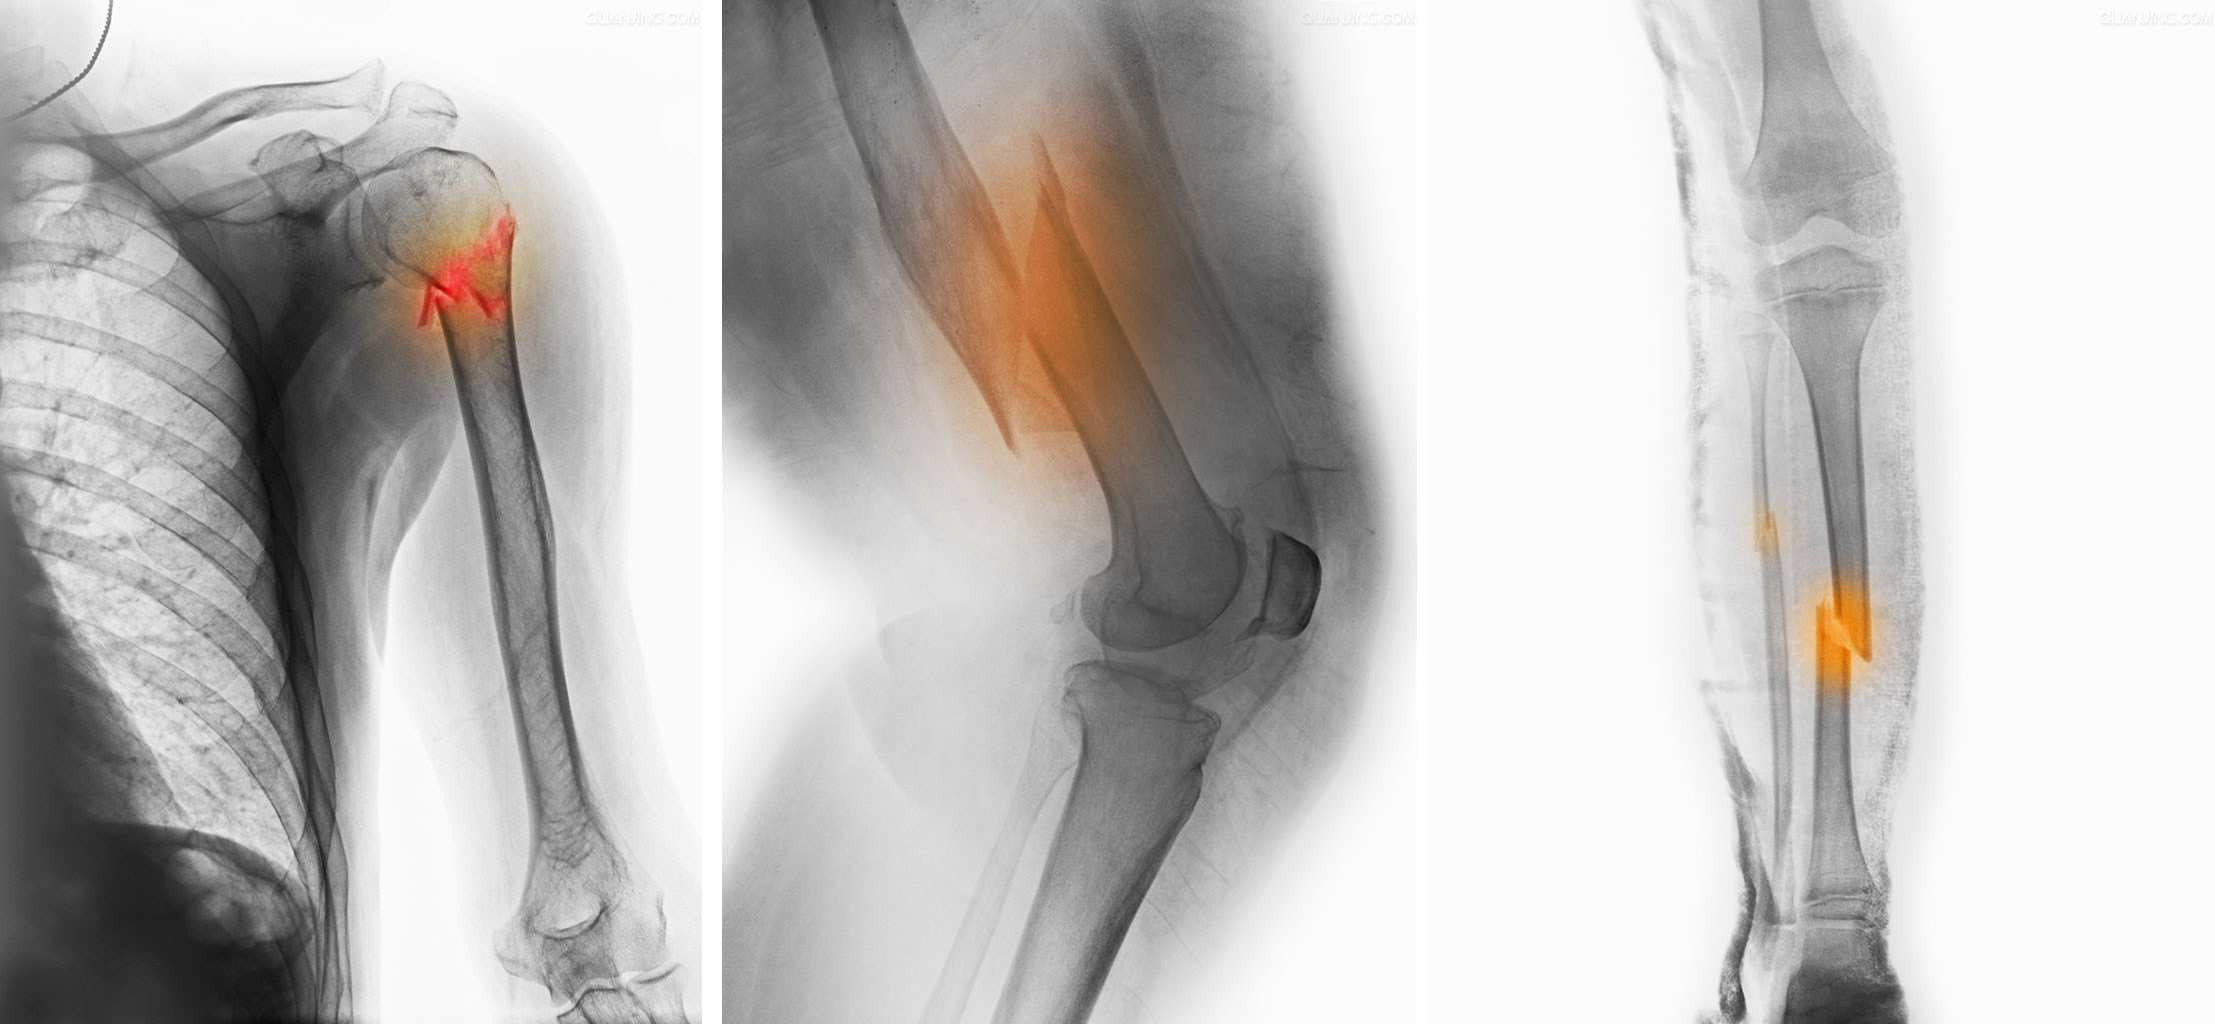

1、各类四肢骨折脱位:特别对于关节周围骨折,通过微创和传统手术治疗,减少关节骨折致残、畸形、功能不良的后遗症。

2、老年骨质疏松骨折:对于高龄、内科合并症较多的骨质疏松骨折,发挥多学科合作的优势实施综合治疗。广泛应用微创的手段,治疗高龄老人常见的脊柱压缩骨折、髋部骨折、桡骨远端骨折、肱骨近端骨折等骨质疏松骨折。

3、擅长处理严重创伤:如肢体骨折复杂髋臼骨折;复杂骨盆骨折;骨折合并血管神经损伤;骨折合并软组织缺损伴骨外露;以及骨折不愈合、骨折畸形愈合矫正等。